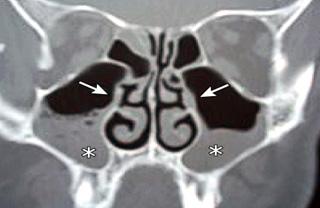

Exámenes

Para todos los pacientes con colesteatoma, se obtiene una tomografía computarizada (TC) del hueso temporal. Estas imágenes pueden ayudar a definir la extensión de la enfermedad, ya sea que haya erosión, formación de fístulas o afectación intracraneal o laberíntica. La resonancia magnética (MRI) es más sensible y debe solicitarse (sin

y con gadolinio) cuando se sospecha de complicaciones intracraneales (p. Ej., Extensión directa o meningocele o encefalocele).